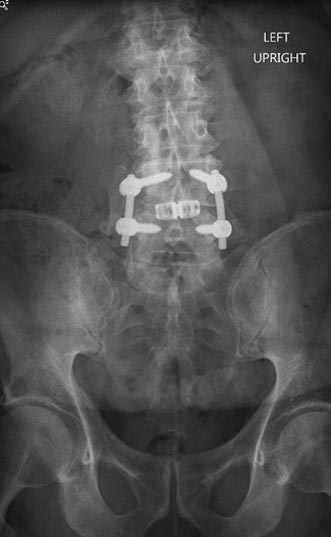

73 year old woman with osteoporosis who fell and fractured her pelvis. She was unable to walk and developed lumbopelvic dissociation (seperation of the spine from the pelvis and lower half of the body) from an unstable sacral fracture and displacement.

Lumbopelvic fixation with prophylactic cement augmentation and patient was immediately able to walk again.